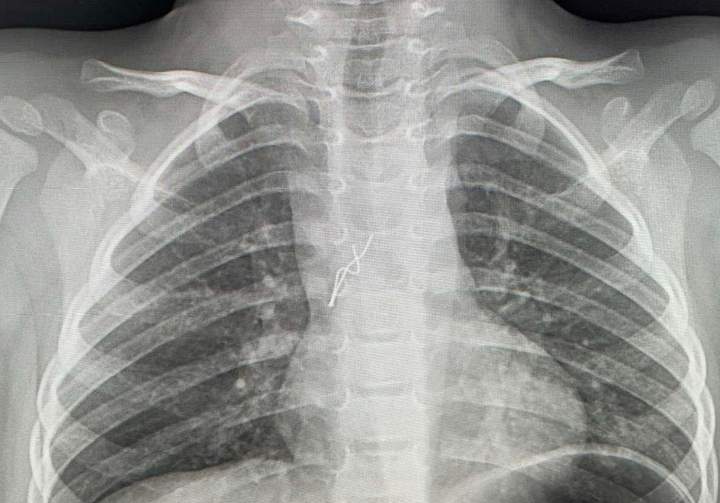

У Львові 4-річний хлопчик проковтнув лампочку з гірлянди і почав кашляти та задихатися. Батьки викликали швидку, яка доставила дитину до львівської обласної дитячої лікарні «Охматдит».

Лікарі відразу зробили рентген і у бронхах виявили стороннє тіло – світлодіодну лампочку з гірлянди. Гострі краї вже встигли травмувати слизову бронха. Хлопчика відразу повезли в операційну.

Лікарі діставали предмет за допомогою бронхоскопії, тобто без жодного розрізу.

"Гострими, направленими в різні сторони вусиками лампочка "дивилася" на мене. Вуса під час дихання травмували слизову оболонку в ділянці біфуркації трахеї, там уже утворилися дрібні крововиливи. Я захопив вусики щипцями і завів їх у тубус бронхоскопа, щоб під час видалення не травмувати ними бронхи і трахею. Разом з тубусом дістав лампочку з бронха дитини", — пояснив торакальний хірург Олександр Колодій.